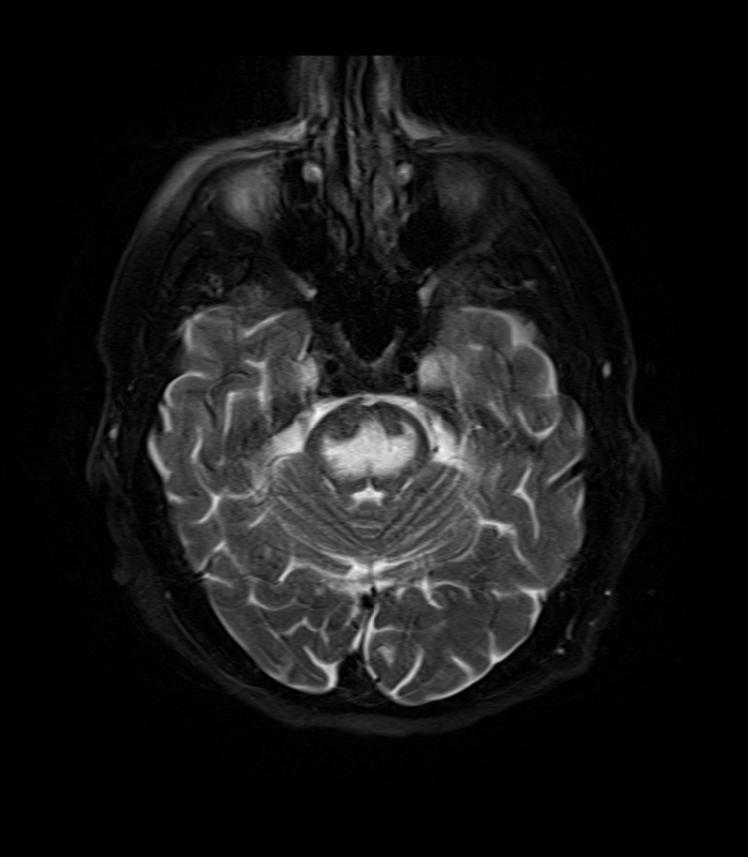

Central pontine myelinolysis is focal demyelination of the pons (anterior brain stem) due to rapid intravenous hyponatremia correction.

Locked in syndrome is the result of central pontine myelinolysis.

Locked in syndrome is characterized by acute bilateral paralysis.